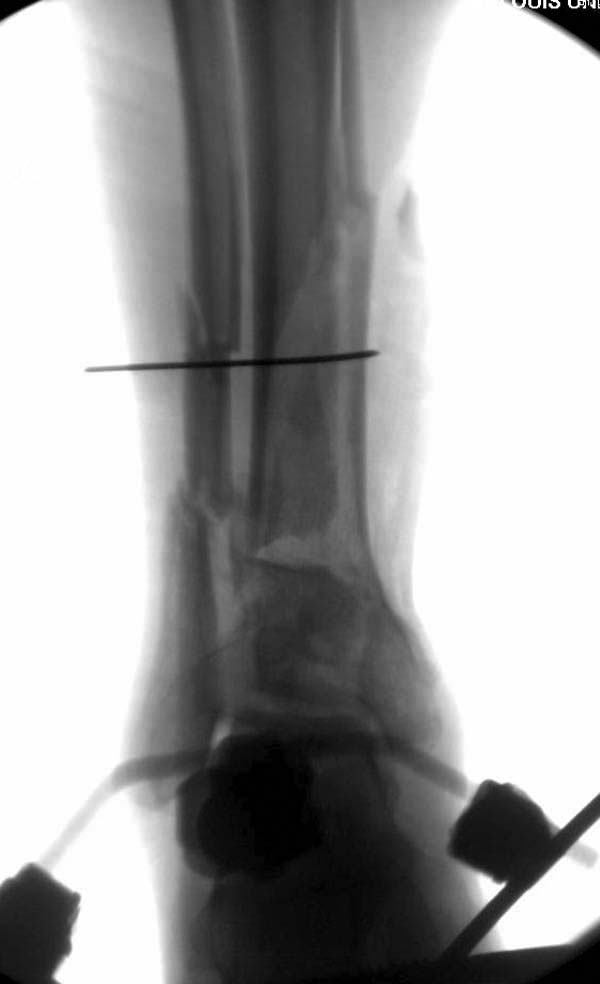

Через три дня повторная I&D, где через рану манипулировали дистальным фрагментом с установкой пары межфрагментарных шурупов. На рану вакуум и следующая обработка закончилась закрытием раны. Отек держался немного дольше, чем обычно.

После спадения отека вариантов фиксации много, включая мининвазивную технику, но данный случай закончили установкой простого аппарата Илизарова.